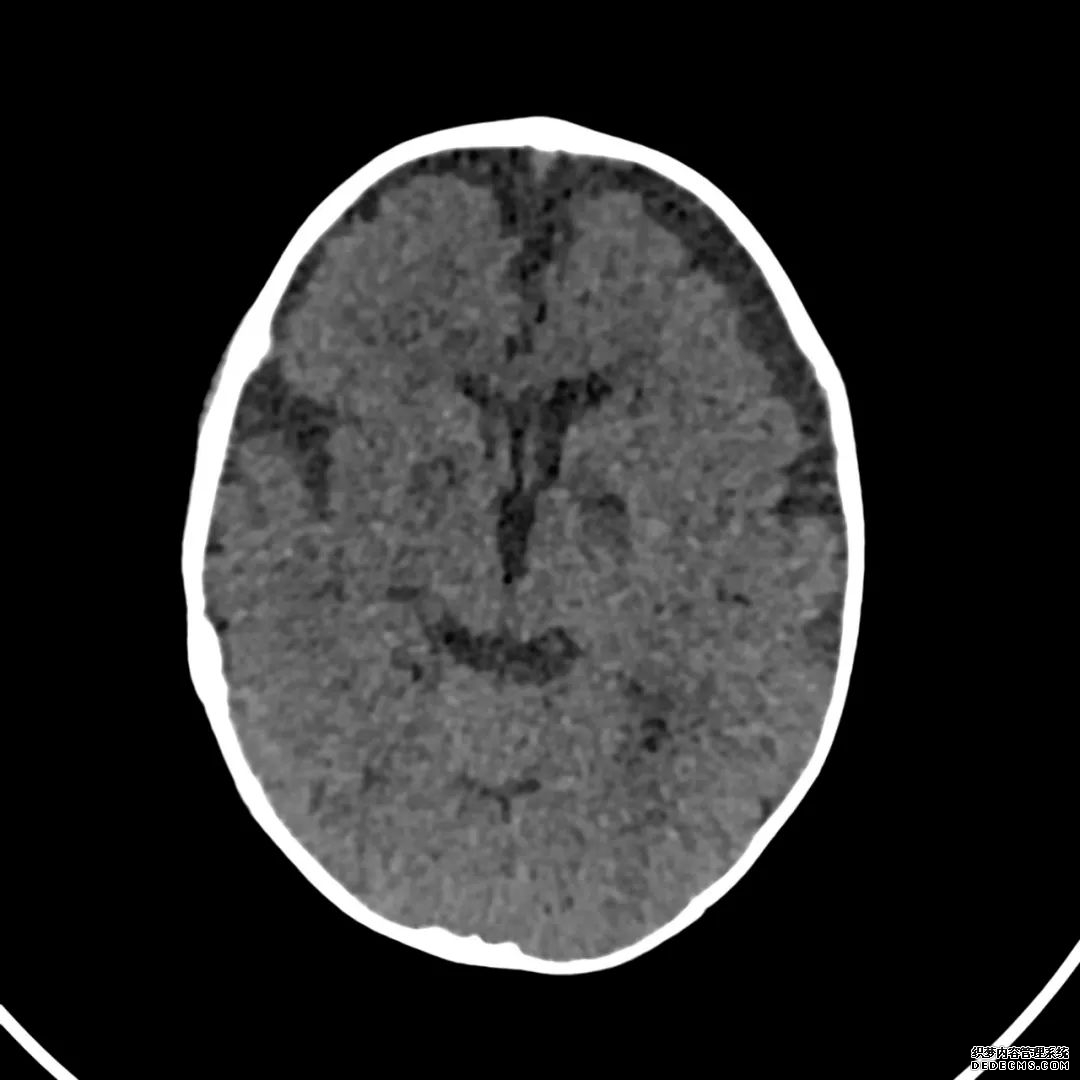

脑部CT检查显示扁豆状核内有略对称的低密度区。

脑MRI显示尾状核、扁豆状核和脑梗头部T2/FLAIR呈双侧对称异常高信号。扩散限制涉及这些区域,其特征是扩散加权DWI(B-1000)上的高强度,ADC图上相应的减弱强度。

印象:通过将这些成像模式与临床和实验室检查结果相结合,就有可能得出低血糖性脑病。

影像影响内囊后肢、大脑皮层(特别是枕叶和岛叶)、海马和基底节区,常是双边对称性的。